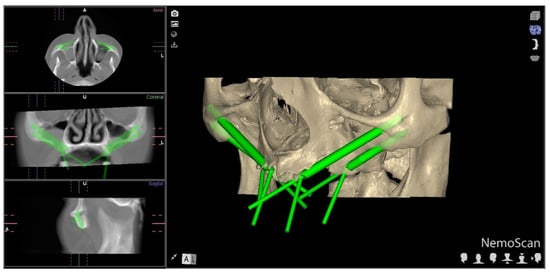

2.2. Experimental Procedure